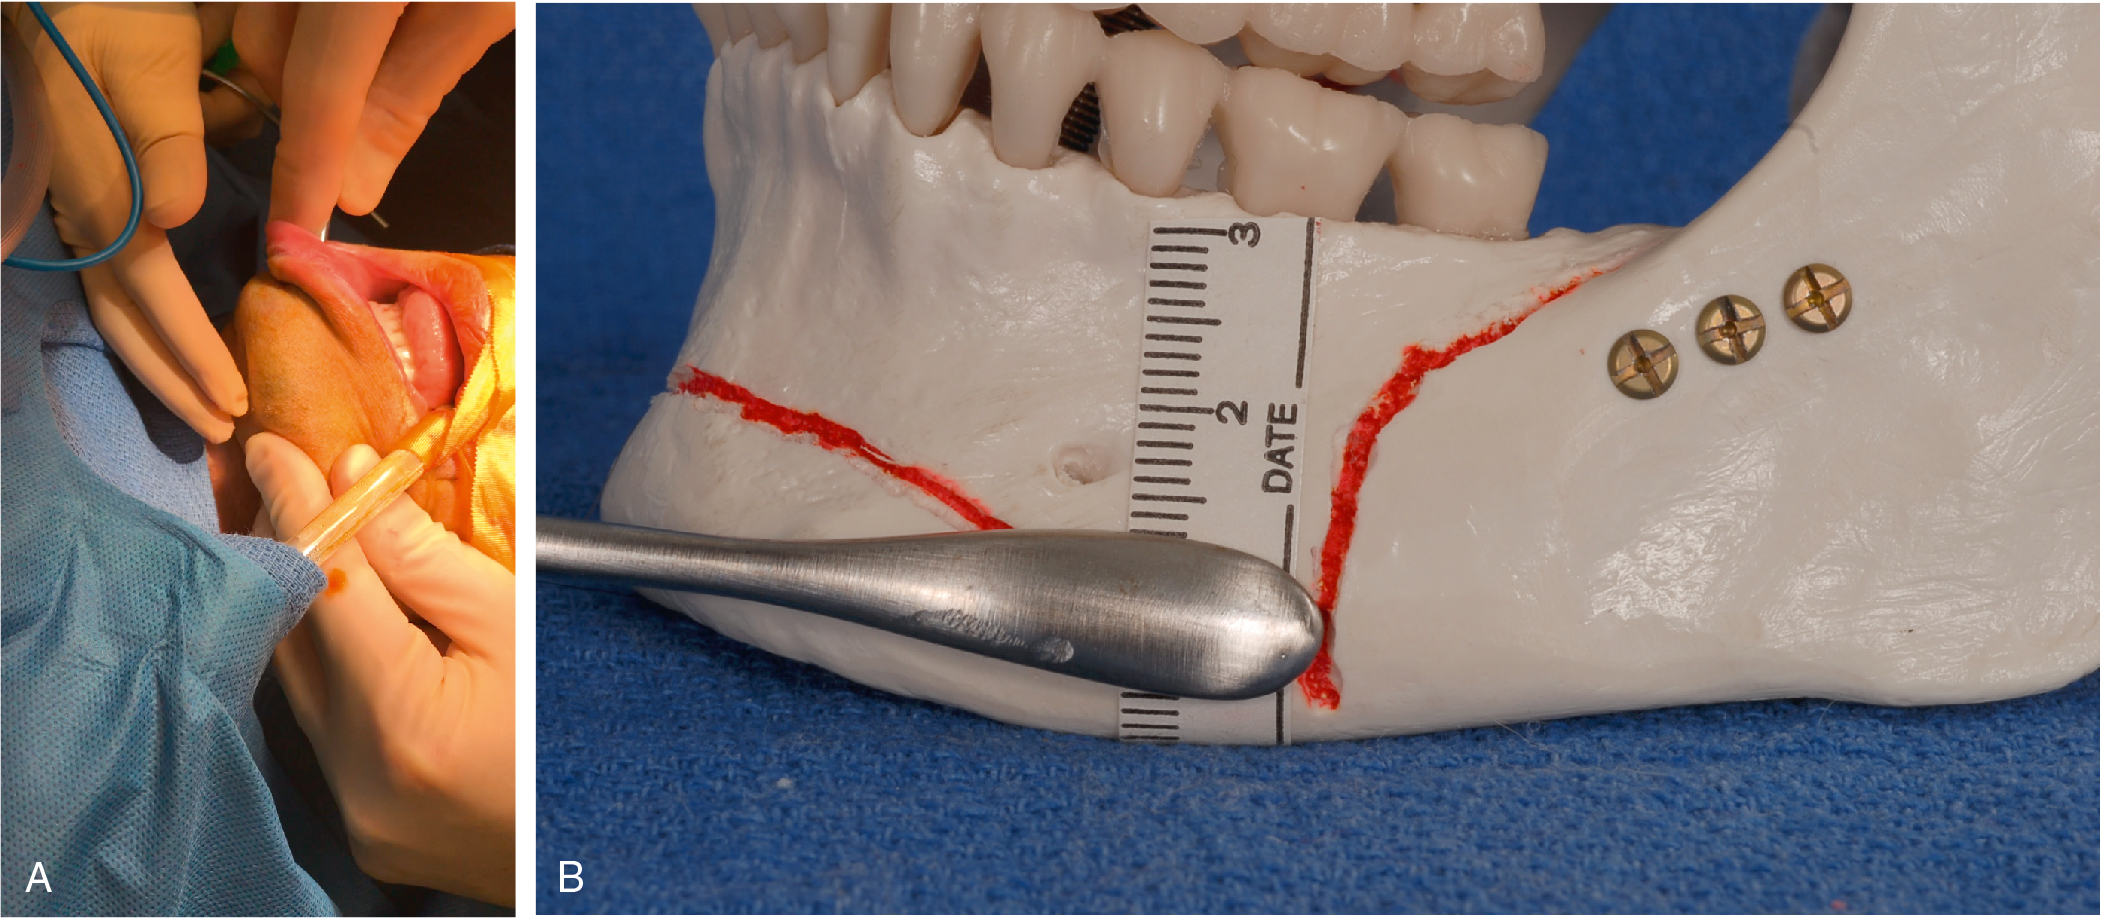

Use the nondominant hand to evert the lip, using the index finger to palpate below the intraoral incision.

- •

Using a guarded blunt tip Bovie, make the initial mucosal incision from canine to canine then redirect the Bovie toward the bone to divide the mentalis muscle. The left index finger is used to make sure that the Bovie tip does not inadvertently cut through the cutaneous surface ( Fig. 27.1 ).

Fig. 27.1

The lip is everted, and the nondominant index finger is placed under the everted lip to palpate the electrocautery tip and to ensure that the surgeon does not inadvertently buttonhole the incision.

A periosteal elevator is then used to dissect from the incision to the inferior border of the mandible in an inferior direction. Once the inferior border has been identified, the periosteal elevator can be used to dissect laterally in the subperiosteal plane along and parallel to the inferior aspect of the mandible. Because the mental foramen is 14 mm superior to the inferior mandibular border and the widest Obwegeser periosteal elevator is 10 mm wide, this dissection can be done rapidly and blindly without worry of hitting the mental nerve as long as the surgeon keeps the elevator flush with the inferior border of the mandible. We refer to this region as a dissection “hot lane,” meaning the dissection can be done very quickly without risk of injury to the mental nerve. Once this dissection has been done bilaterally, careful superior elevation easily identifies the mental nerve ( Fig. 27.2 ).

Fig. 27.2

(A) The Obwegeser periosteal elevator is placed such that the edge is adjacent to the inferior border of the mandible. The location is confirmed by palpation, and the surgeon can advance the elevator laterally in a subperiosteal plane to dissect the pocket rapidly. As long as the elevator’s inferior edge is congruent with the inferior border of the mandible, there is little risk of injuring the nerve, and the dissection can be done blindly. (B) The widest of the Obwegeser periosteal elevators is 10 mm. The distance from the inferior border of the mandible to the mental foramina has been shown to be 14.61 mm. Given that there is a 5-mm safety margin, a rapid blind subperiosteal dissection can be performed as long as the edge of the elevator hugs the inferior edge of the mandible.